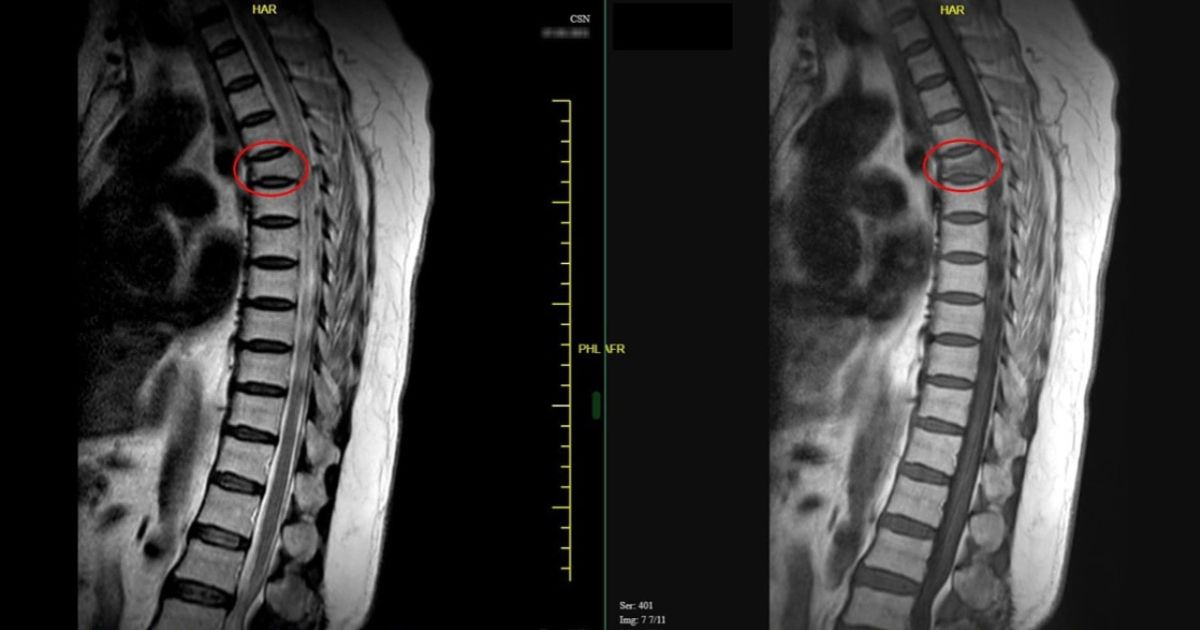

Các bác sĩ sẽ đánh giá sự phục hồi của đốt sống sau khi bơm xi măng qua phim chụp